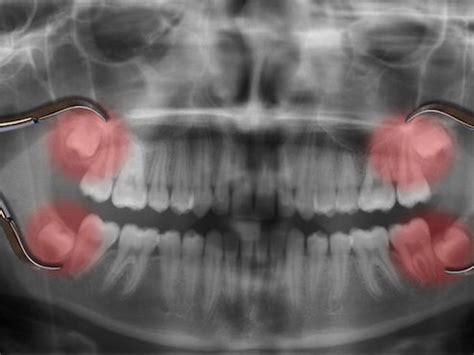

Evaluación previa: Antes de programar la cirugía, examinaremos tu boca y tomaremos radiografías panorámicas o 3D. Así podemos ver la posición de las muelas del juicio y su relación con el hueso, los senos maxilares (en el caso de superiores) o el nervio dentario inferior (en el caso de inferiores). Con esta información, planificamos la extracción de la forma más segura.

La facilidad o dificultad con la que tu dentista o cirujano maxilofacial puede extraer las muelas de juicio depende de su posición y desarrollo. El especialista tendrá una idea de qué esperar a partir de los exámenes preoperatorios. Un tercer molar que salió completo, normalmente se puede extraer con la misma facilidad que cualquier otro diente. Pero si está debajo de las encías, más incrustado en el maxilar, si puede requerir una incisión, eliminar una porción de hueso, por lo que requerirá un proceso de extracción más complicado.

Acceso a la muela: Si la muela del juicio ya salió parcialmente, simplemente la tomaremos con instrumentos especiales. Si está incluida o impactada (atrapada bajo la encía o el hueso), haremos una pequeña incisión en la encía para descubrirla. Es posible que necesitemos remover un poco de hueso alrededor o cortar la muela en partes para extraerla con mayor facilidad. Todo esto suena aparatoso, pero ten en cuenta que estarás anestesiado/a: no duele, aunque sí puedes oír el sonido de los instrumentos o notar vibración.